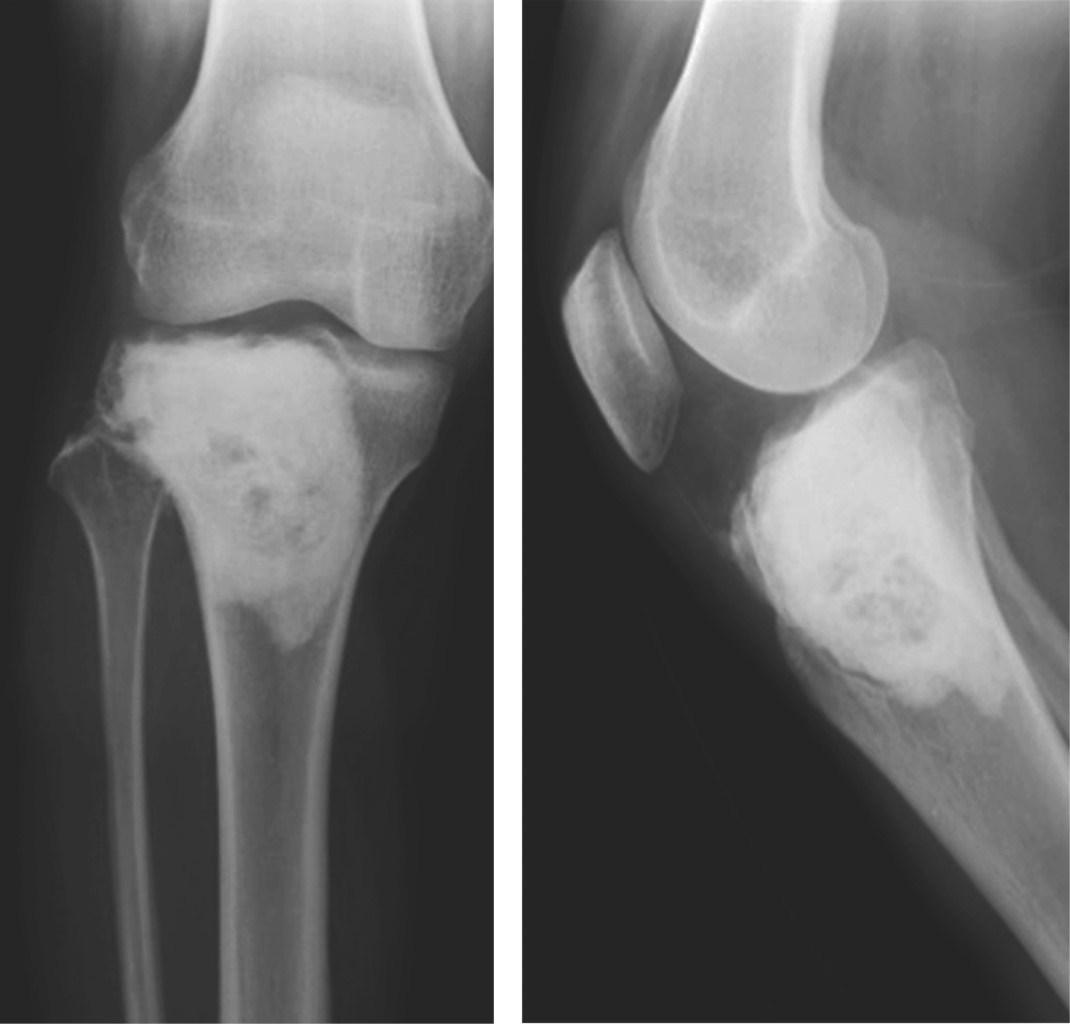

Estudios de laboratorio y gabinete: las imágenes radiológicas iniciales mostraron una lesión en región metafisaria proximal de la tibia, bien delimitada, lítica, de bordes escleróticos, lobulada y expansiva (Figura 1). Se realizó protocolo de estudio, encontrándose exámenes de laboratorio dentro de límites normales.

Figura 1